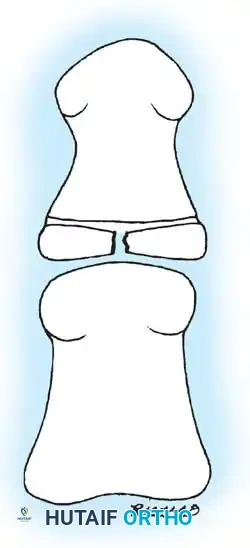

Fig. 33-171: Classification of floating knee injuries in children. (Redrawn from Letts M, Vincent N, Gouw G: The “floating knee” in children, J Bone Joint Surg 68B:442, 1986.)

The "floating knee" describes an ipsilateral fracture of the femur and tibia, creating a flail knee joint. These are high-energy injuries often associated with polytrauma. The Letts classification (Types A through E) categorizes these based on whether the fractures are open or closed, and whether they involve the diaphysis or the metaphysis/epiphysis.